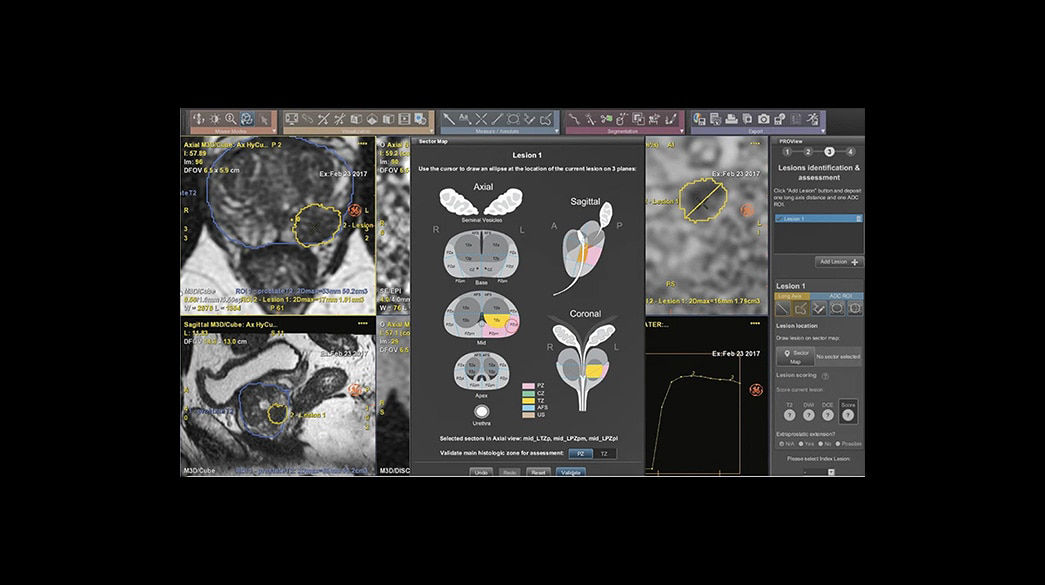

Quantifiable

Provides quantitative and actionable information